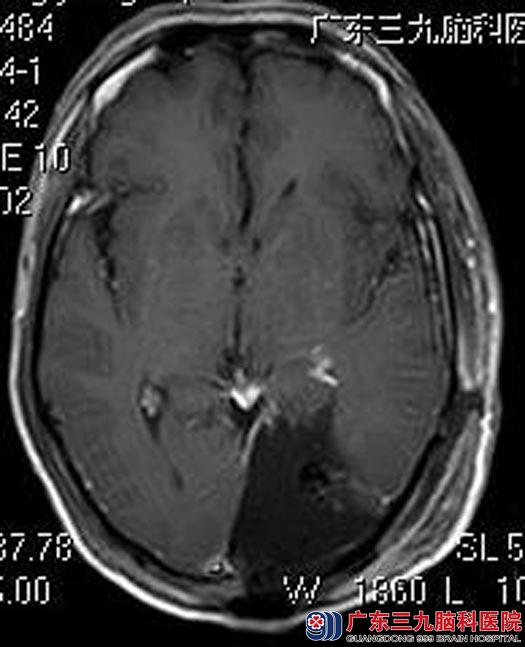

在广东三九脑科医院综合神经外科体格检查:精神食欲差,双侧瞳孔等圆等大,直径约2.5mm,对光反射灵敏,左眼视力4.7(0.5)、右眼视力4.5(0.3),双眼右侧偏盲。头颅MR检查显示:左侧顶枕部占位性病变,大小约3.8cm×6.4cm×5.9cm,考虑胶质瘤。

由鲁明主任主刀在全麻下行“左侧顶枕叶肿瘤切除术”,术中见肿瘤实质部分邻近中线,质软,呈灰白色胶样,血供较丰富,于显微镜下顺利全切除。术后谢先生的头痛头晕、恶心呕吐不适症状消失,视野较前好转,康复出院。术后病理结果提示:间变型星形细胞瘤WHO III级。